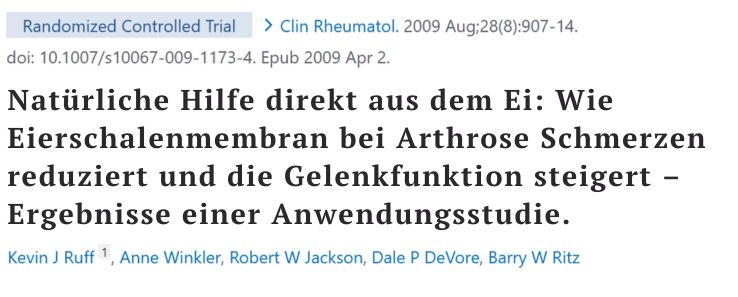

Der innovativste Durchbruch aus der Forschung ist hier die Eierschalenmembran. Diese enthält einen natürlichen Komplex aus verschiedenen Typen Kollagen, Hyaluronsäure, Glucosamin, Chondroitin und weiteren Proteinen – und zwar genau in der Struktur, wie sie auch im Knorpel vorkommt. Der natürliche Aufbau in der Membran kann vom Körper deutlich besser aufgenommen und genutzt werden als künstliche Einzelstoffe. Klinische Studien belegen, dass Eierschalenmembran Arthroseschmerzen und Steifheit signifikant reduzieren kann.

3. Rubaxx Komplex

Platz 3 belegt Rubaxx Komplex vom selben Hersteller. Hier bekommt man ein Pulver zum Auflösen.

Wie vermutet enthält es die Bausteine Kollagenhydrolysat, Glucosamin, Chondroitin und Hyaluronsäure, ergänzt durch viele Vitamine und Mineralstoffe, darunter auch die Co-Faktoren Vitamin C, D, K und Mangan.

Doch hier zeigt die Analyse eine deutliche Schwäche: Eine Wirkfolge für Knorpelschutz, Schmerzlinderung und Knorpelaufbau fehlt.

Und statt der hochwertigen, natürlichen Eierschalenmembran-Matrix setzt es auf die künstlich zusammengestellten Standard-Bausteine (Glucosamin, Chondroitin etc.), deren Bioverfügbarkeit extrem gering ist.

Positiv war der Geschmack des aufgelösten Pulvers für Tester, die auf sehr süße Getränke stehen.

Das führt zu einem weiteren Kritikpunkt – den enthaltenen Zusatzstoffen. Das Pulver enthält Aroma, das künstliche Süßungsmittel Sucralose und Maltodextrin – einen Industriezucker. Zusätze, die Entzündungen sogar verschlimmern können.

Der Beipackzettel zeigt: Erste Zutat Industriezucker (Maltodextrin).

Das Produkt ist relevant durch verschiedene Vitamine, überzeugt einige Tester im Geschmack, zeigt aber trotz PZN ein fehlendes Gesamtkonzept.